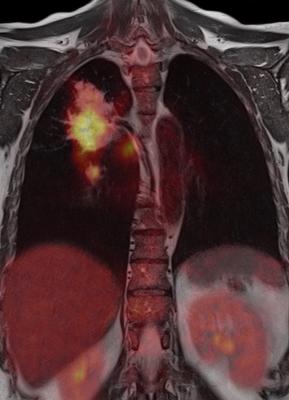

Most PET scans use a tracer that can only tell if a tumor is active in terms of its metabolism. In this case, F-MPG can tell doctors whether the tumor cells are present and whether they contain a mutated version of a protein called epidermal growth factor, which when overexpressed spurs cell division. The F-MPG tracer floats throughout the body, glomming onto any mutated epidermal growth factor proteins. Once latched on, it emits blips of detectable energy in the form of gamma rays, revealing the location and mutational details of the culprit protein.

"If the PET scan shows a high signal from the tracer in a patient's lung cancer, that's predictive of someone who is going to respond well to the specific epidermal growth factor therapy," Gambhir said. "For those who show low signals, they're likely not going to respond, so you need to look into other treatment options."

At Harbin Medical University, members of the research team conducted a 75-participant clinical trial with the tracer, monitoring which tumors lit up (or had a high signal) on a PET scan and which had a low signal. Among the participants whose tumors appeared with the help of the tracer – meaning their tumor cells had the epidermal growth factor mutation – more than 80 percent saw a positive response from the targeted drug: Either their tumors shrank or tumor growth slowed. In contrast, only 6 percent of participants who lacked PET scan evidence of the mutation benefited from the drug.